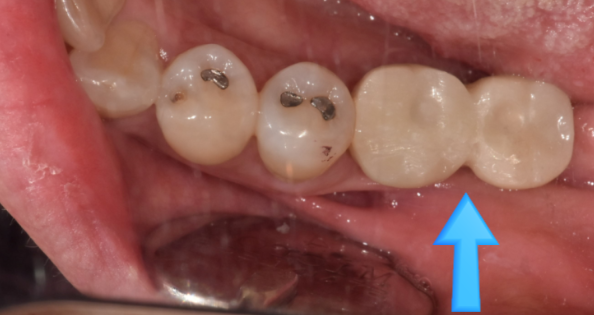

잇몸 안에 임플란트를 묻어 둔 경우

임플란트 수술한게 맞냐는 질문을 많이들 해주십니다.

230707

그도 그럴 것이 사진과 같은 모습이기 때문이죠~!

잇몸밖에 안보이죠~?